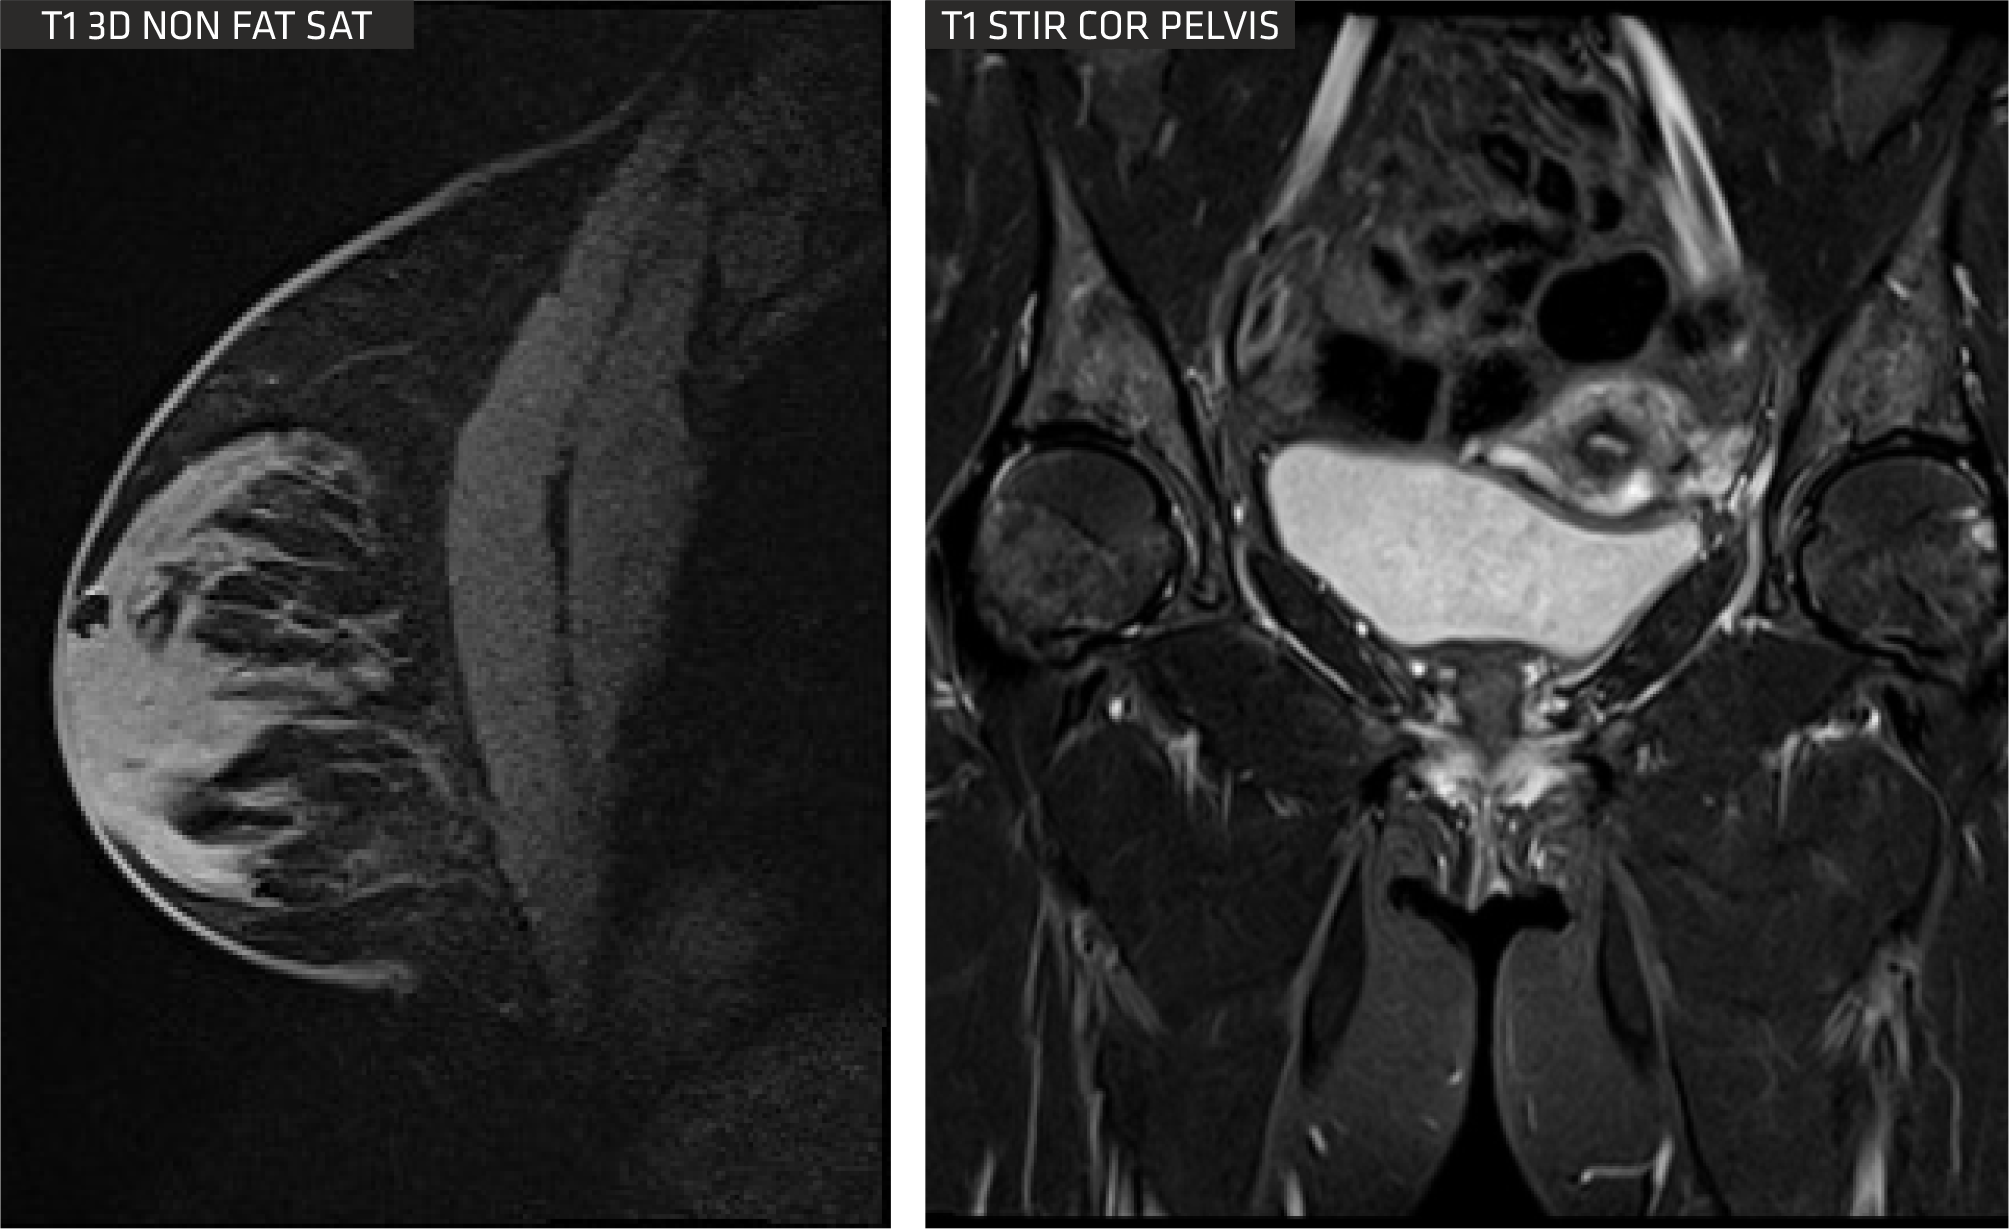

Advanced Body imaging

The Sequoia Healthcare Clarity 1.5T oers comprehensive body imaging solutions with advanced tools tailored for patients. Its Free Breathing (ARCUS) MR Imaging protocols primarily utilize either breath-holding techniques or respiratory gating to eectively minimize motion-related artifacts, ensuring clearer and more accurate imaging results.

A visualization platform is available, granting access to sophisticated postprocessing technology. Leveraging the Proton Density Fat Fraction (PDFF) method, it automatically segments and measures fat within the liver by creating quantitative fatfraction maps.